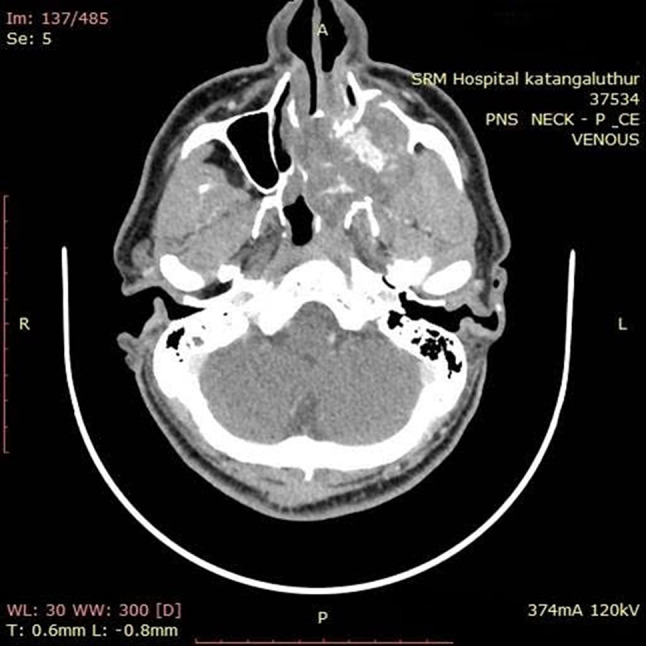

Contrast Enhanced Computed Tomography (CECT) scan and Magnetic Resonance Imaging (MRI) screening of the paranasal sinuses were done, suggesting a slow flow vascular malformation, most likely a Cavernous hemangioma, or less likely an expansile vascular neoplastic lesion (Fig. 1).

Fig. 1.

Axial CECT scan showing soft tissue density mass in the left maxillary sinus, with puddling of contrast in arterial and gradual filling in delayed phase, with extension, mass effect, bony erosions